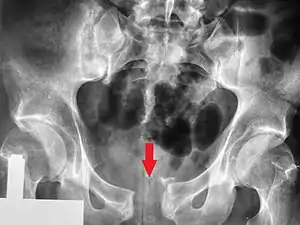

Pelvic vertical shear fracture

Fractures of the superior (in two places) and inferior pubic rami on the person's right, in a person who has had prior hip replacements